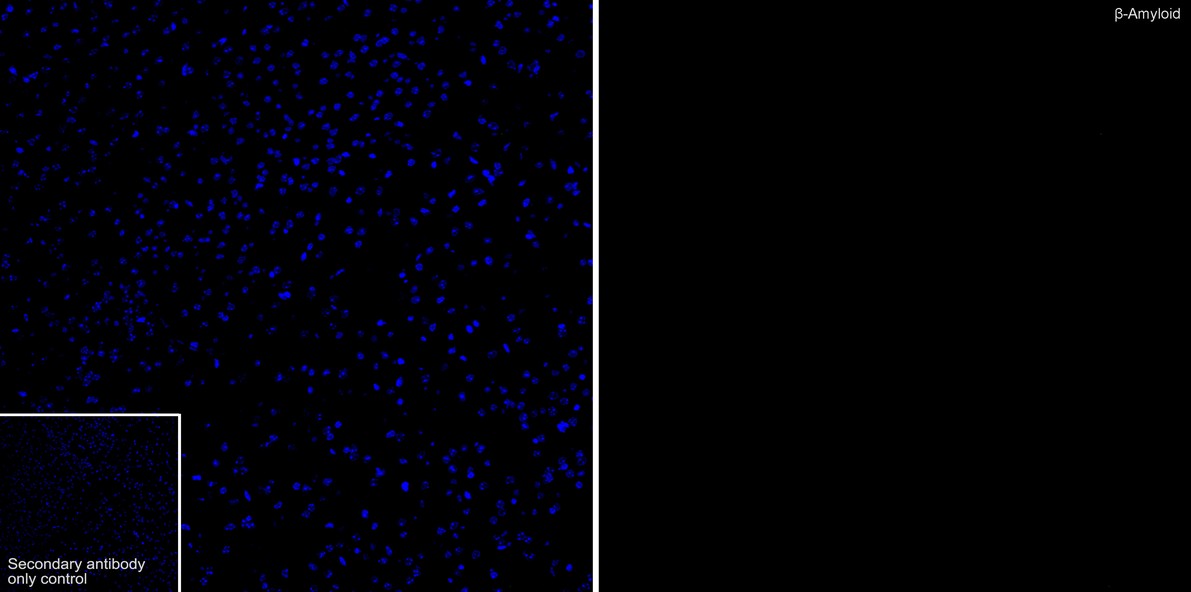

HA751210_4.jpg Fig4: Immunofluorescence analysis of paraffin-embedded mouse brain tissue (negative control) labeling beta Amyloid with Rabbit anti-beta Amyloid antibody (HA751210) at 1/50 dilution.

The section was pre-treated using heat mediated antigen retrieval with Tris-EDTA buffer (pH 9.0) for 20 minutes. The tissues were blocked in 10% negative goat serum for 1 hour at room temperature, washed with PBS, and then probed with the primary antibody (HA751210, green) at 1/50 dilution overnight at 4 ℃, washed with PBS. Goat Anti-Rabbit IgG H&L (iFluor™ 488, HA1121) was used as the secondary antibody at 1/1,000 dilution. Nuclei were counterstained with DAPI (blue).